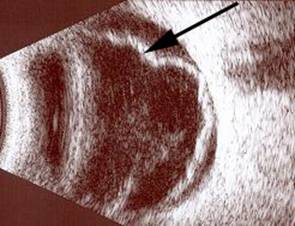

Resim 4: Retina dekolmanı olan hastanın ultrasonografi görüntüsü. Retinanın yerinden ayrıldığı öne doğru yer değiştirdiği izlenmektedir (siyah ok).